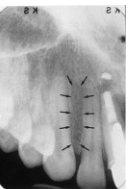

Maxillary Sinus

radiolucent area located above the apices of the premolar/molar areas in maxilla

(radiolucent)

Maxillary Tuberosity

radiopaque bulge distal to last tooth on max arch

(radiopaque)

Hamulus

radiopaque pointy projection located distal to max tuberosity

Zygomatic Arch

J or U shaped radiopaque area superior to the maxillary 1st molar region

What surrounds the maxillary sinus?

septa

What appears in the area of the maxillary canine and premolars?

inverted-y

(radiopaque, upside down y)